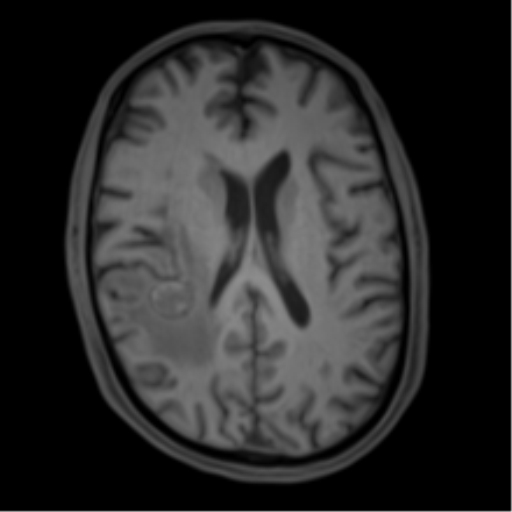

Изображения и частично текст взяли с радиопедии radiopaedia.org. 1 МРТ Т1, 2 МРТ Т2 (кейс 1), 3 - КТ с контрастом (кейс 2)

Это разделение критически важно для лучевой диагностики. Исследование Isiklar (1995 г.) показало, что характерные признаки МРТ (гиперинтенсивный сигнал на T1 и гипоинтенсивный на T2) сигнал наблюдается только у меланотических метастазов. К сожалению, на их долю приходится лишь около 25% случаев, в то время как амеланотические метастазы имеют неспецифическую картину.

Магнитно-резонансная томография (МРТ)

Ключевой особенностью является высокая частота спонтанных кровоизлияний, что делает меланому одним из самых геморрагичных метастазов наряду с хориокарциномой.

Меланин и продукты распада крови (метгемоглобин) одинаково укорачивают T1- и T2-время релаксации.

Это приводит к сходной картине: гиперинтенсивный сигнал на T1-ВИ и гипоинтенсивный на T2-ВИ.

Различить их влияние на стандартных последовательностях часто невозможно.

Ключевые МР-признаки:

T1-ВИ: Обычно гиперинтенсивный сигнал (за счет меланина и/или крови).

T2-ВИ: Часто гипоинтенсивный.

T1-ВИ с контрастом: Контрастирование по периферическому (ободковому) или гетерогенному диффузному типу.

*T2 (GRE) / SWI:** Важный диагностический признак. Выраженные артефакты магнитной восприимчивости (гипоинтенсивный "ободок") связаны в первую очередь с геморрагическим компонентом (гемосидерин), а не с меланином, который обладает слабым диамагнитным эффектом.

Артефакты восприимчивости встречаются в 42% случаев метастазов меланомы (для сравнения, при метастазах рака легкого — лишь в 8%).

Некоторые мелкие метастазы могут быть видны только на T2*/SWI, однако интерпретировать изолированные гипоинтенсивные очаги на этих последовательностях следует с осторожностью.